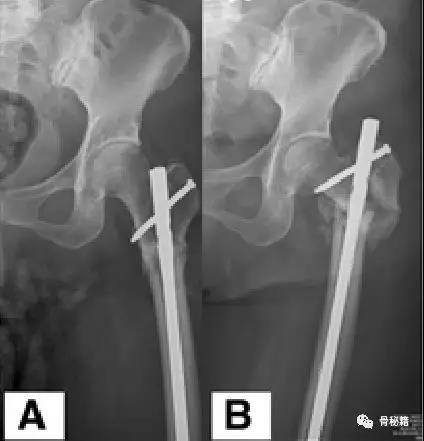

一个双膦酸盐治疗5年的患者粗隆下非典型骨折

采用了髓内钉固定,术后一年内固定失效

更换了DCS+植骨固定,术后四个月又发现了内固定失效再次更换了更长的DCS

这次的固定能成功吗?